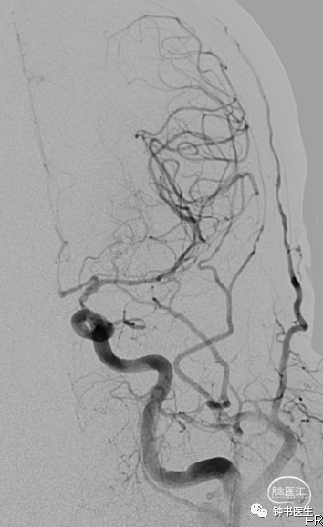

2019-1-13

神经重症治疗思路

血压:90-100mmHg(100-120mmHg)

灌注压:50mmHg(60-70mmHg)

脱水:四联

深度镇静镇痛(咪达唑仑+瑞芬)

ICP:10mmHg以内(1-12mmHg)

2019-1-14

2019-1-16

神经重症治疗思路

血压:90-100mmHg

灌注压:60mmHg

脱水:三联

镇静镇痛(咪达唑仑+瑞芬)

ICP:10mmHg以内

2019-1-19